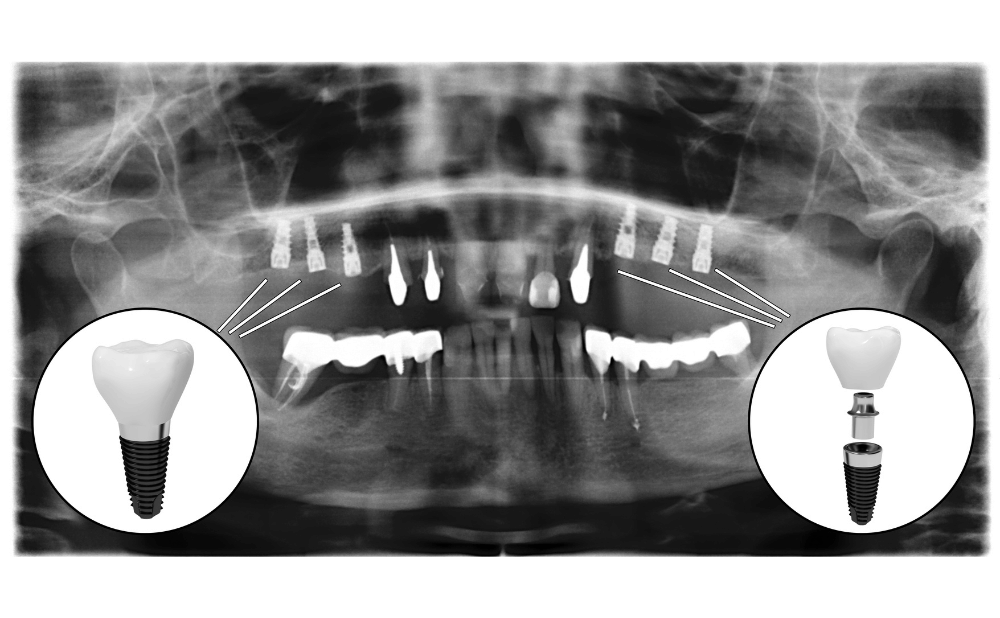

オールオンフォーは顎の骨に固定される治療で、食事中に装置がずれたり外れたりする心配がありません。

固定式のオールオンフォーと可撤式の総入れ歯では、噛む力が異なります。

顎の骨が痩せてしまい、通常のインプラント治療が難しい症例でも、適用できる可能性が高いです。